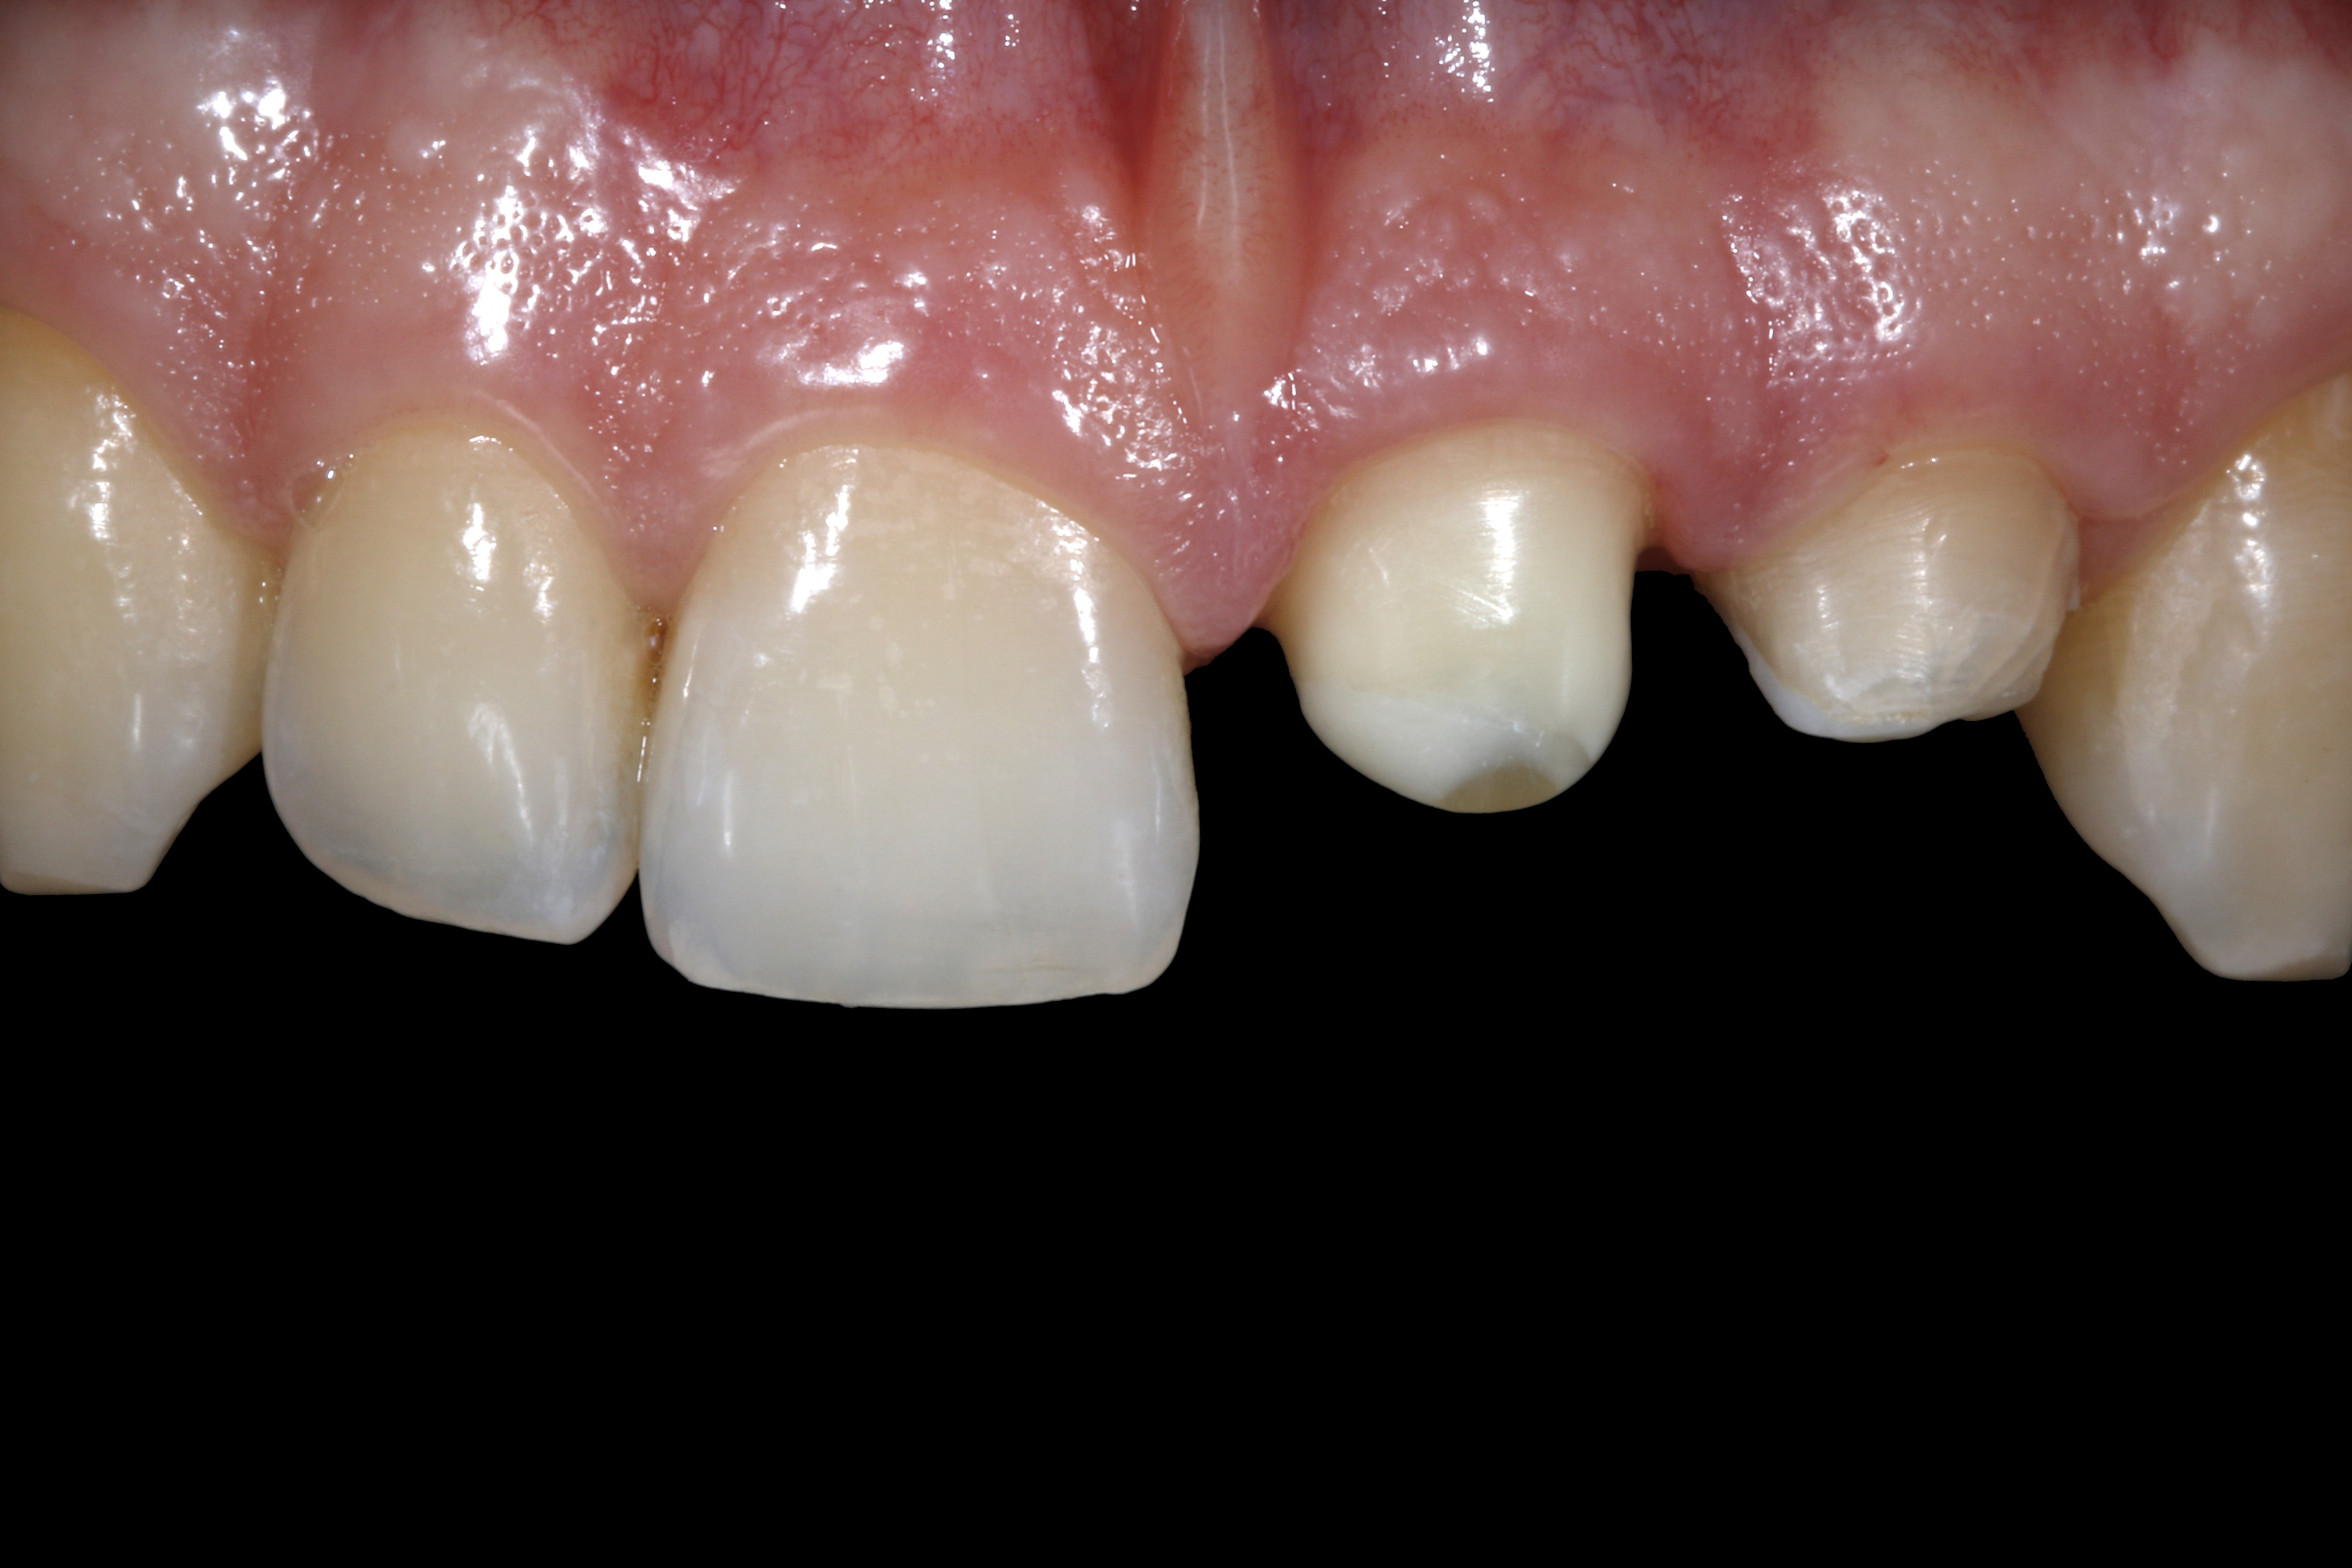

Ryc. 3. Sytuacja po opracowaniu zęba 21 do korony. Podczas kolejnej wizyty zaplanowano usunięcie zęba 22 i przeprowadzenie natychmiastowej implantacji. Do czasu wykonania docelowej rekonstrukcji, jako tymczasowe długoczasowe zaopatrzenie w okresie gojenia, należy wykorzystać wykonaną w pracowni protetycznej koronę na ząb 21, z przęsłem dowieszonym w okolicy zęba 22.